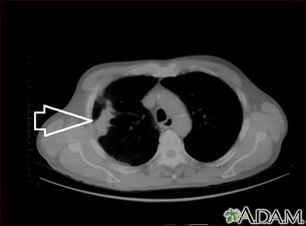

Lung mass, right lung - CT scanBackLung mass, right lung - CT scanThis is a CT scan of the upper chest showing a mass in the right lung (seen on the left side of the picture). E-mail FormEmail ResultsName:Email address:Recipients Name:Recipients address:Message: